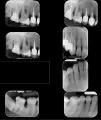

Мне 23. У меня сейчас режется зуб мудрости. Был в стоматологии, сказали, что зуб растёт хорошо и не криво. До посещения у меня были боли в области челюсти, виска и скулы.

Однако после посещения, после того, как стоматолог инструментом поковырялся у меня в десне у зуба мудрости, у меня стал очень сильно болеть рядом стоящий зуб (рядом с зубом мудрости). При нажатии на зуб или лёгком надавливании на него случайно или при смыкании челюсти возникает сильная боль. Если всё же до упора нажать на зуб, то после сильной боли, боль немного притупляется и воздействие на зуб вызывает боль чуть менее сильную. Рядом с зубом мудрости и последующим зубом воспалилась десна.